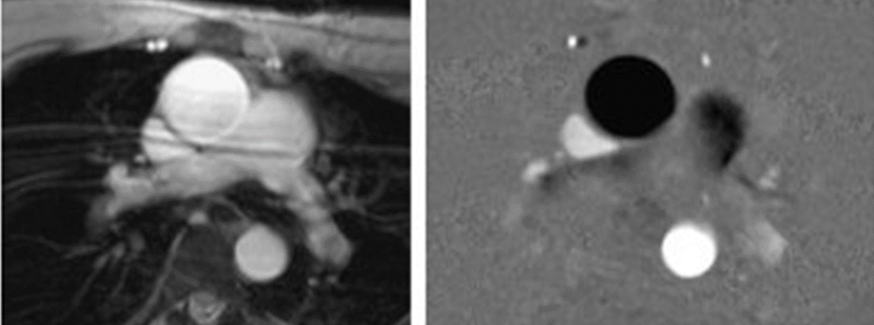

Cardiac Imaging

MRI is considered gold standard for myocardial thickness and changes in the relaxivity due to chemotherapy and other injury. T1- T2-, T2* maps can be created.

Click images for larger view and description

• Myocardial thickness

• Relaxivity due to chemotherapy or other injury